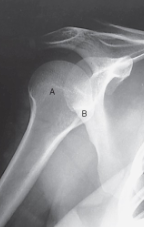

label the anatomy accordingly A-G, the projection/part, and rotation if applicable

head of humerus, greater tubercle, intertubercular sulcus, lesser tubercle, anatomic neck, surgical neck, body

AP shoulder — external rotation